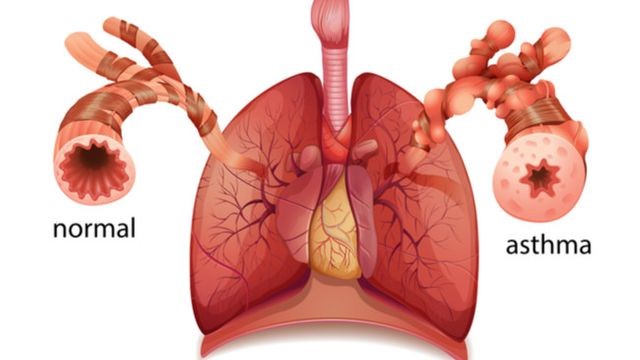

Asma

Demikian gambar keluhan Asma yang sangat berbahaya itu.